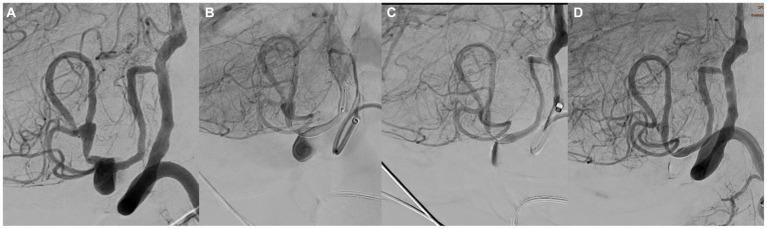

Long-term follow-up of cerebral aneurysms treated with the Silk Vista Baby (SVB) flow diverter is lacking. This study aimed to assess the technical success, procedural safety, and efficacy of the SVB (Balt, Montmorency, France) for the treatment of intracranial aneurysms in small cerebral vessels over a mid-to long-term follow-up.

We retrospectively analyzed a prospectively maintained database of patients treated with the SVB between September 2018 and June 2021. Data regarding patient demographics, aneurysm characteristics, and technical procedures were also collected. Angiographic and clinical findings were recorded during the procedure and over a period of at least 12 months.

Angiographic and clinical follow-up data were available for 50 patients/50 aneurysms. The procedural complication rate was 8%. At 12 months, the final results showed a technical success rate of 100%, the re rupture rate was 0%, neuromorbidity and mortality rates of 4 and 0%, respectively, and an almost complete occlusion rate of 94%.

缺乏对使用Silk Vista Baby(SVB)血流导向装置治疗脑动脉瘤的长期随访。本研究旨在评估SVB(法国蒙特莫朗西巴尔公司)在中长期随访中治疗小脑血管内颅内动脉瘤的技术成功率、手术安全性和疗效。

我们回顾性分析了2018年9月至2021年6月期间接受SVB治疗患者的前瞻性维护数据库。还收集了患者人口统计学、动脉瘤特征和技术操作的数据。在手术期间及至少12个月的时间内记录血管造影和临床结果。

50例患者/50个动脉瘤有血管造影和临床随访数据。手术并发症发生率为8%。在12个月时,最终结果显示技术成功率为100%,再破裂率为0%,神经功能障碍率和死亡率分别为4%和0%,几乎完全闭塞率为94%。